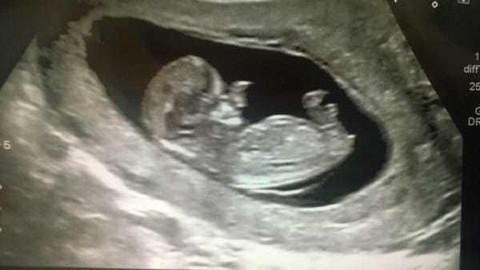

Bebeği bu halde dünyaya geldi görenler gözlerine inanamadı 3 yıl sonra...

Galerinin tamamı için tıklayınızAmy, çocuğundan yine de vazgeçmedi ve onu dünyaya getirdi 'Onu kucağıma ilk aldığımda açıklaması zor, büyük bir şok yaşadım'

Amy, çocuğundan yine de vazgeçmedi ve onu dünyaya getirdi 'Onu kucağıma ilk aldığımda açıklaması zor, büyük bir şok yaşadım'